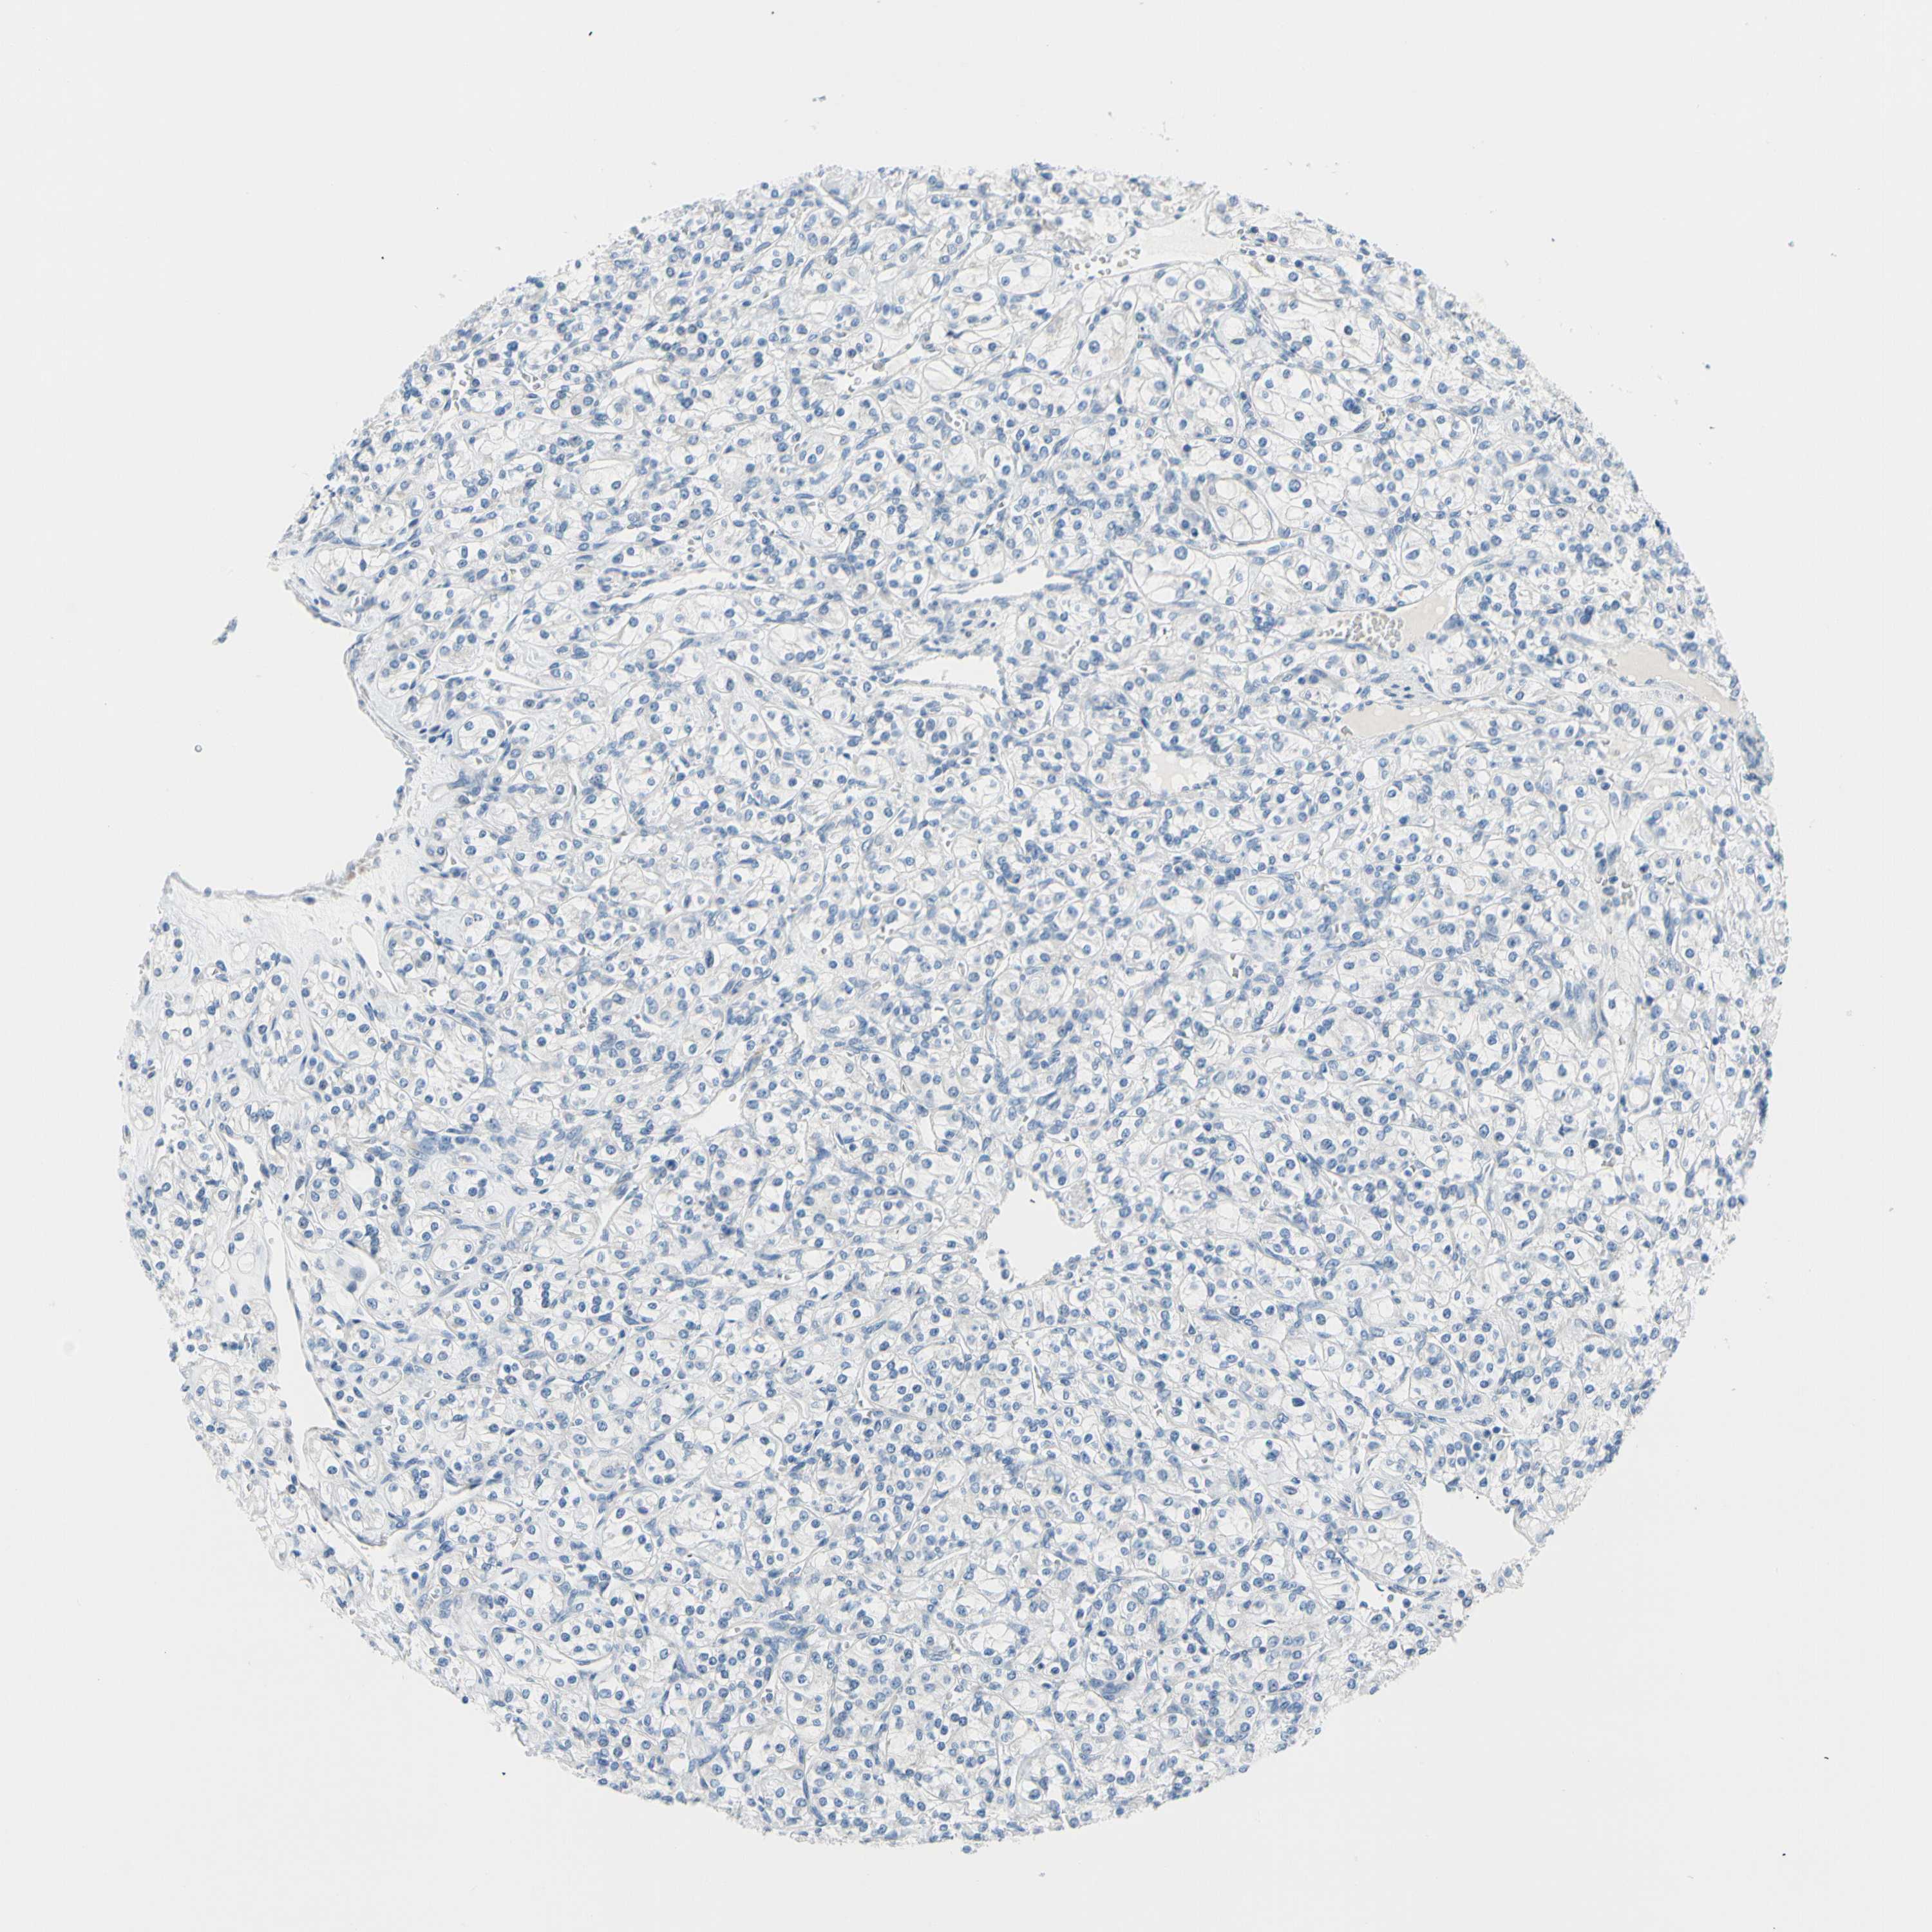

KIDNEY RENAL PAPILLARY CELL CARCINOMA (TCGA) - Interactive survival scatter ploti

The Survival Scatter plot shows the clinical status (i.e. dead or alive) for all individuals in the patient cohort, based on the same data that underlies the corresponding Kaplan-Meier plots. Patients that are alive at last time for follow-up are shown in blue and patients who have died during the study are shown in red.

The x-axis shows the expression levels (FPKM) of the investigated gene in the tumor tissue at the time of diagnosis. The y-axis shows the follow-up time after diagnosis (years). Both axes are complimented with kernel density curves demonstrating the data density over the axes. The top density plot shows the expression levels (FPKM) distribution among dead (red) and alive patients (blue). The right density plot shows the data density of the survived years of dead patients with high and low expression levels respectively, stratified using the cutoff indicated by the vertical dashed line through the Survival Scatter plot. This cutoff is automatically defined based on the FPKM cutoff that minimizes the p-score. The cutoff can be changed by dragging the vertical line or by entering a cutoff value in the square labeled "Current cut-off".

Under the Survival Scatter plot the p-score landscape (black curve; left axis) is shown together with dead median separation (red curve; right axis). Dead median separation is the difference in median mRNA expression between patients who have died with high and low expression, respectively. It is calculated as follows: median FPKM expression of dead patients with high expression - median FPKM expression of dead patients with low expression. This is intended to aid the user in visually exploring custom cutoffs and the associated p-scores and dead median separation.

Individual patient data is displayed and can be filtered by clicking on one or more of the category buttons on the top of the page. Categories describing expression level and patient information include: high, low, alive, dead, female, male and tumor stages. The scale of the x-axis can be toggled between linear and log-scale by clicking on the "x log" button. Mouse-over function shows TCGA ID, patient information and mRNA expression (FPKM) for each patient.

& Survival analysisi

Kaplan-Meier plots summarize results from analysis of correlation between mRNA expression level and patient survival. Patients were divided based on level of expression into one of the two groups "low" (under cut off) or "high" (over cut off). X-axis shows time for survival (years) and y-axis shows the probability of survival, where 1.0 corresponds to 100 percent.

FCER2 is not prognostic in Kidney Renal Papillary Cell Carcinoma (TCGA)

TCGA RNA samplesi

RNA-seq data is reported as average FPKM (number Fragments Per Kilobase of exon per Million reads), generated by the The Cancer Genome Atlas (TCGA) .

Normal distribution across the dataset is visualized with box plots, shown as median and 25th and 75th percentiles. Points are displayed as outliers if they are above or below 1.5 times the interquartile range. FPKM values of the individual samples are presented next to the box plot.

Average pTPM 0.2

Number of samples 282